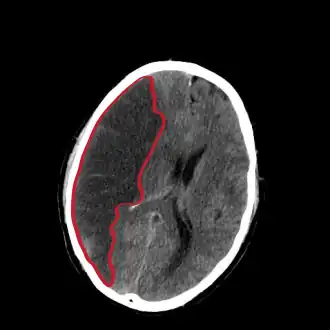

L’infarctus cérébral, appelé aussi accident ischémique cérébral, est un type d'accident vasculaire cérébral. C'est un déficit neurologique soudain d'origine vasculaire causé par un infarctus au niveau du cerveau.

L'infarctus cérébral est causé par une diminution voire un arrêt brutal du débit sanguin dans les branches du réseau vasculaire alimenté par un vaisseau (en général une artère) subissant un blocage partiel ou total (par thrombose, embolie, sténose, ou autre cause pas toujours identifiable).

Ainsi, les cellules nerveuses alimentées par ces branches sont privées soudainement d'oxygène et de sucres, ce qui provoque en quelques minutes leur détérioration ou leur mort.